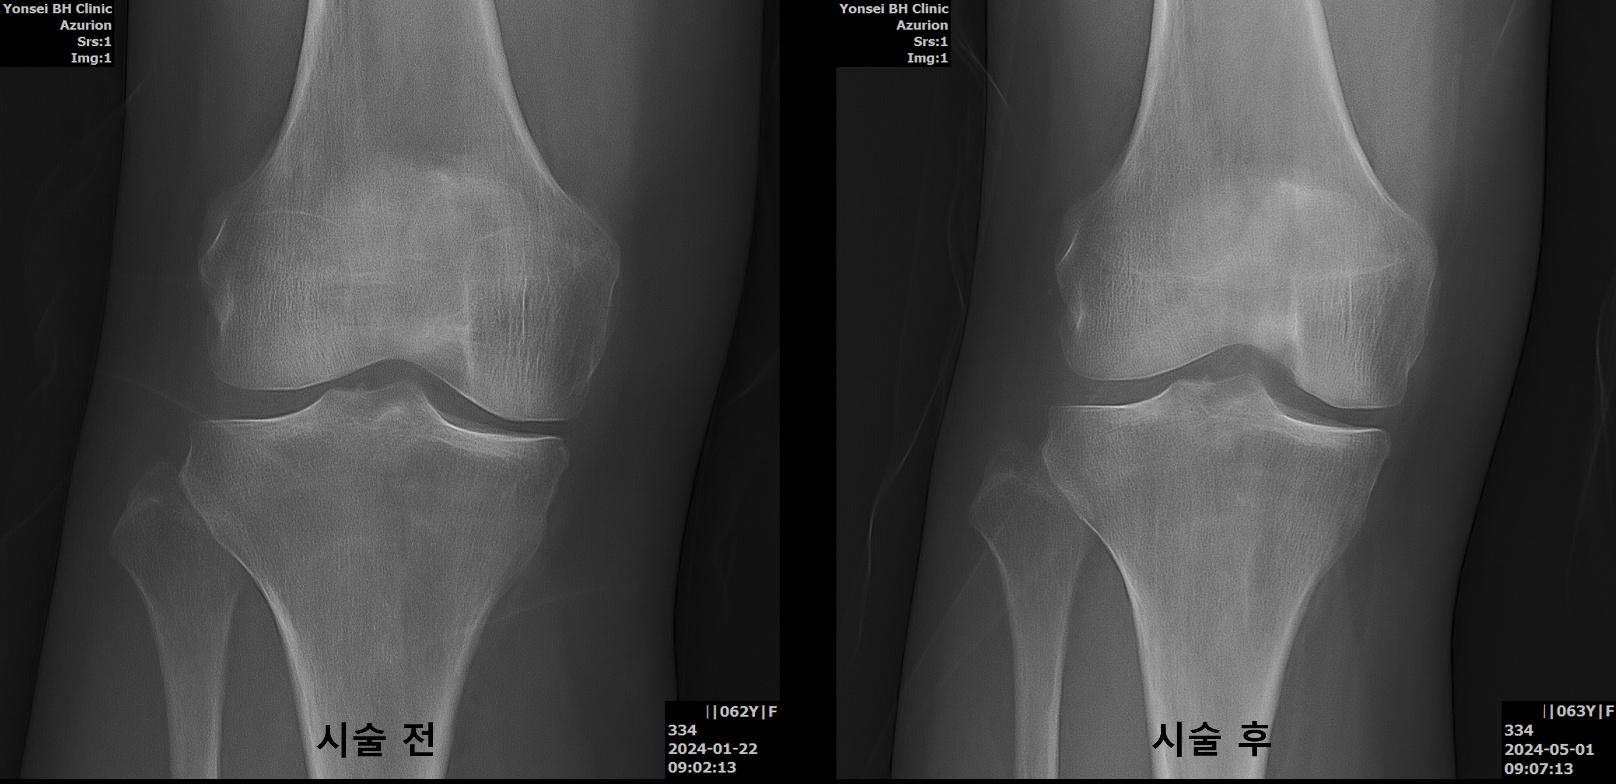

무릎 관절염 치료 시술 전후

무릎관절염 골수 줄기세포 시술 전후 63세 여성